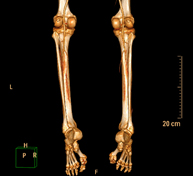

- TC Estudio rotacional EEII (Báscula Rotuliana, distancia TA-GT)

Exploración radiológica que mediante un sistema de rayos X y detectores que giran alrededor del paciente, reconstruyendo las imágenes por ordenador (TC Multidetector), permite calcular una serie de mediciones a nivel de caderas, rodillas y tobillos para solucionar problemas de rotación y angulación de las extremidades inferiores.

- TC Huesos largos

Exploración radiológica que mediante un sistema de rayos X y detectores que giran alrededor del paciente, reconstruyendo las imágenes por ordenador (TC Multidetector), permite el estudio de huesos largos (tibia, peroné, fémur, húmero, radio y cúbito).